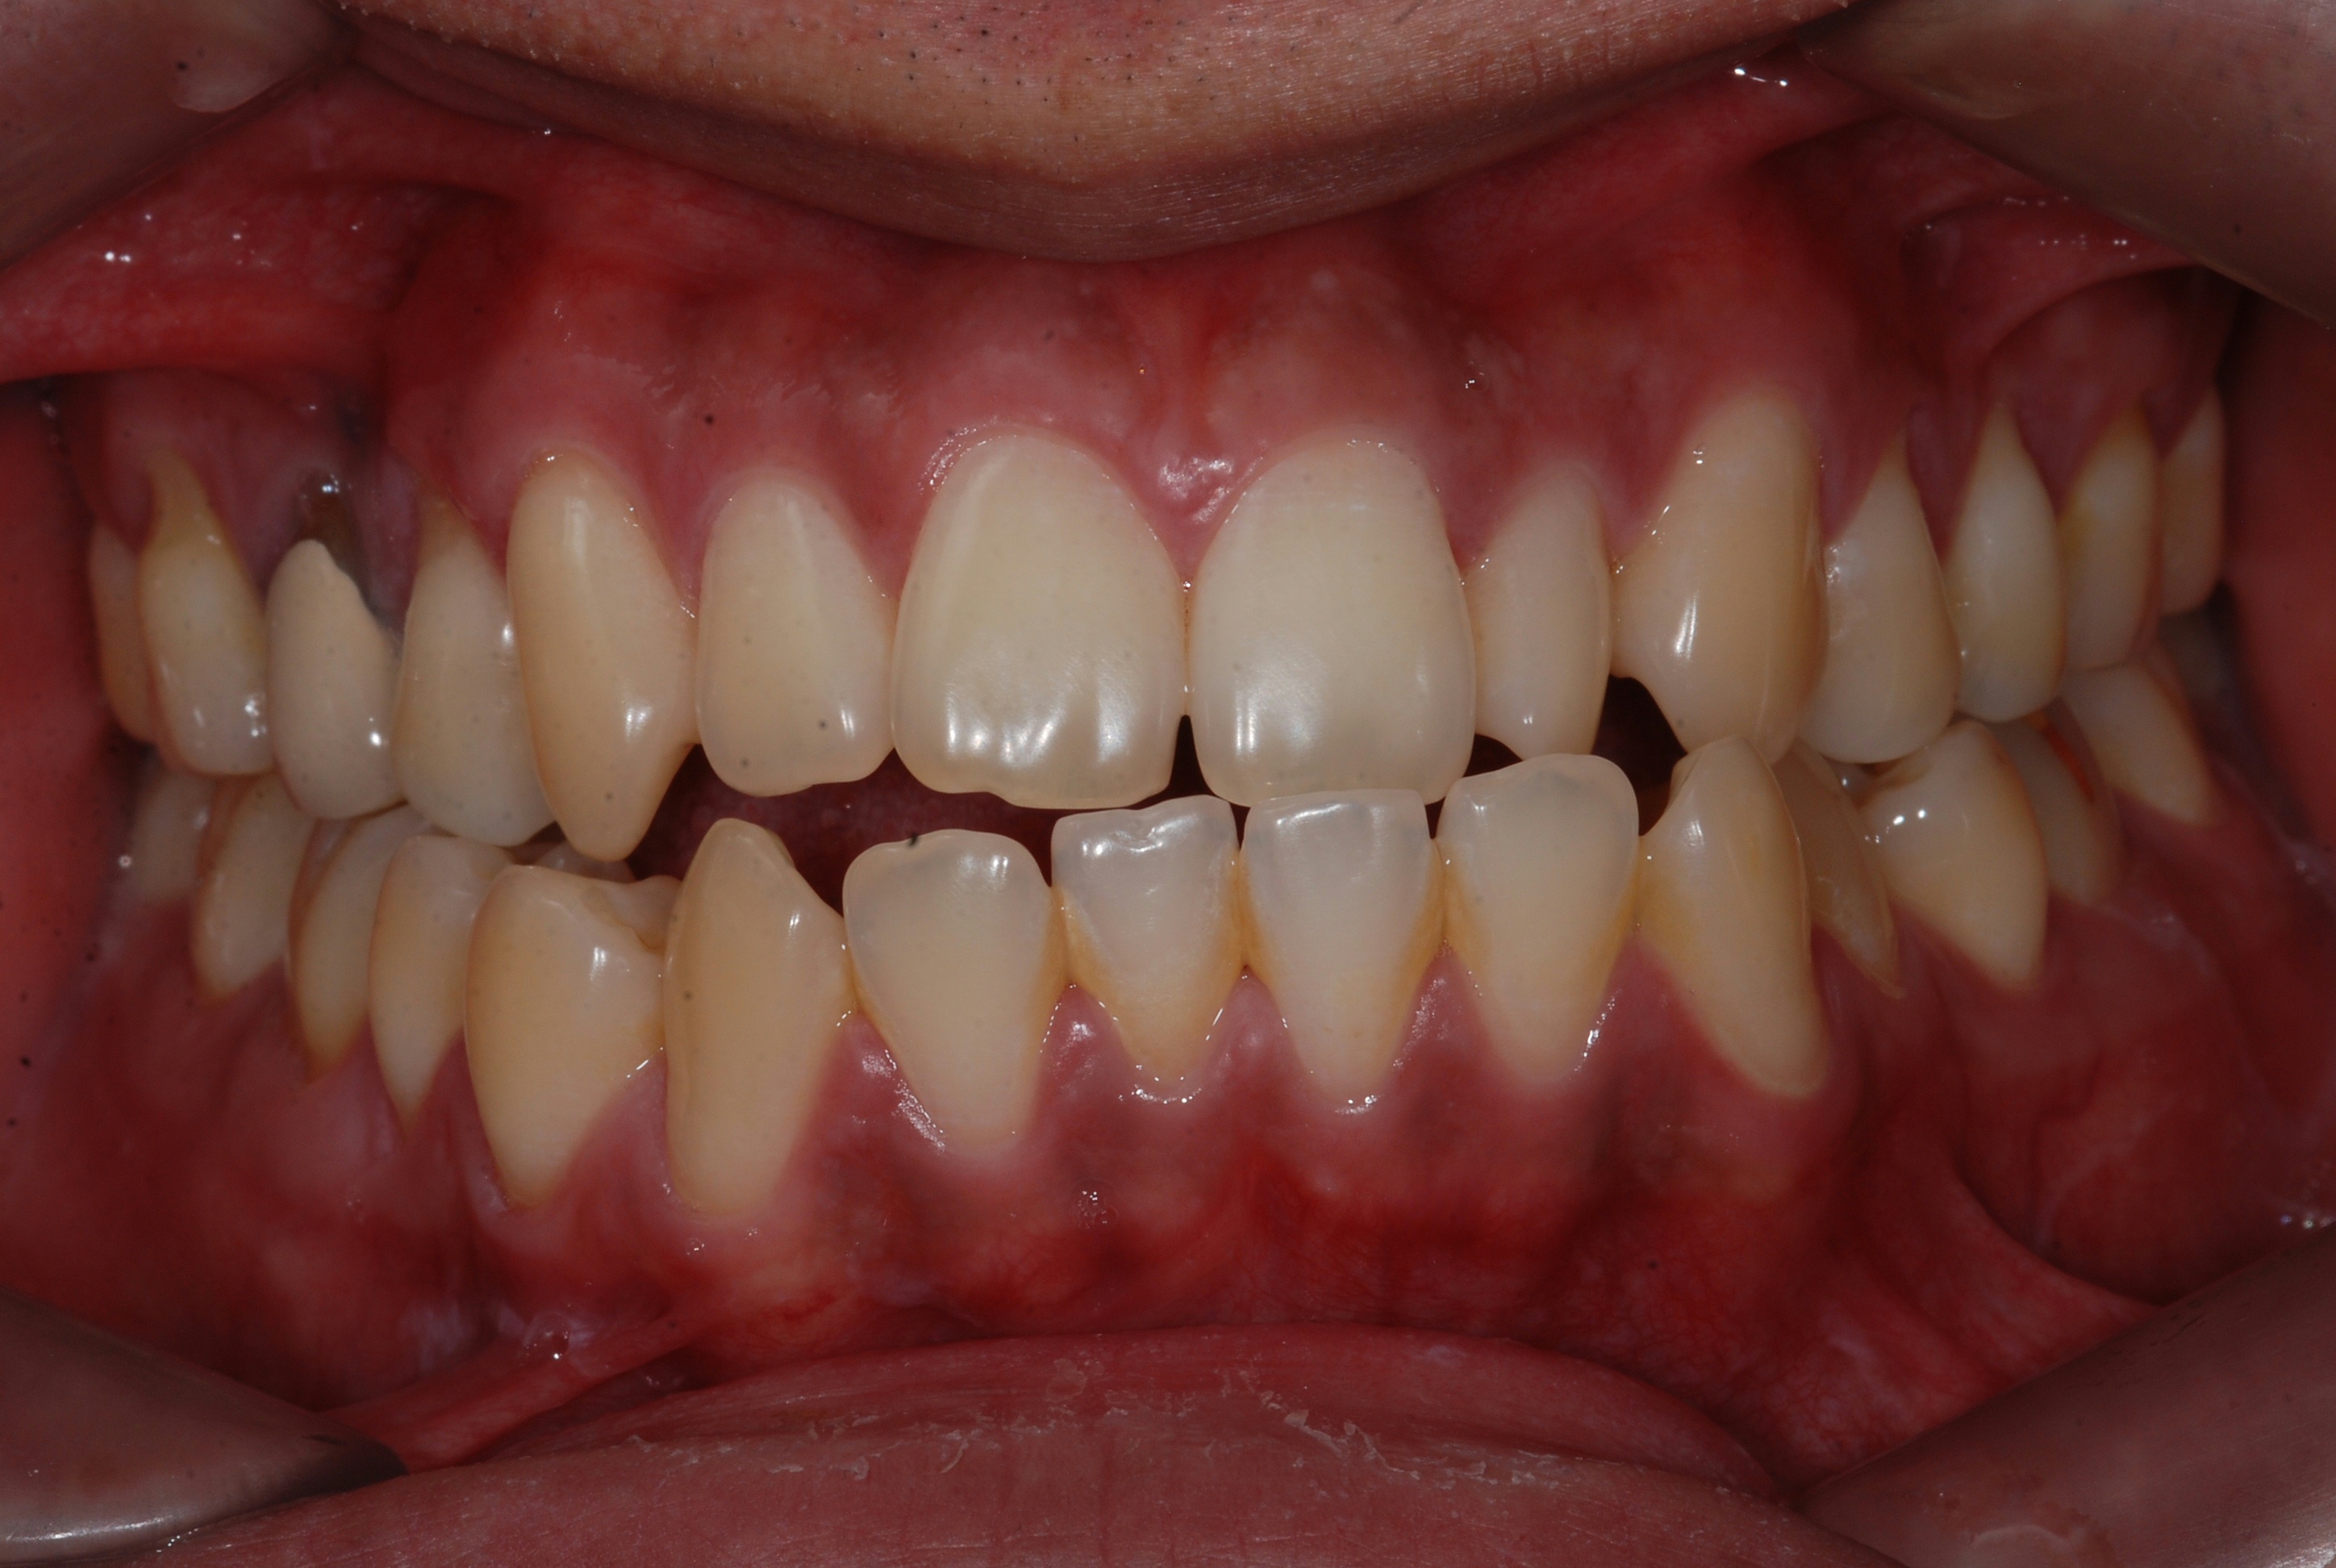

치료 전 사진입니다.